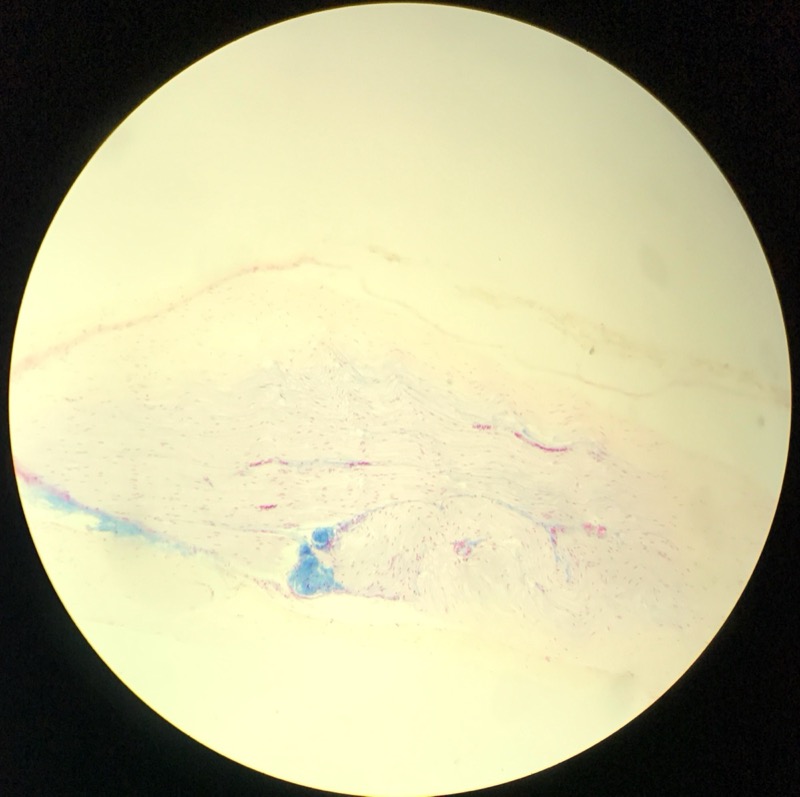

| 1:5:6 | Nagel | ![]() ![]() ![]() ![]() ![]() |